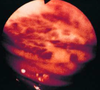

disease and what characterizes it grossly

Barrett’s esophagus

intestinal metaplasia